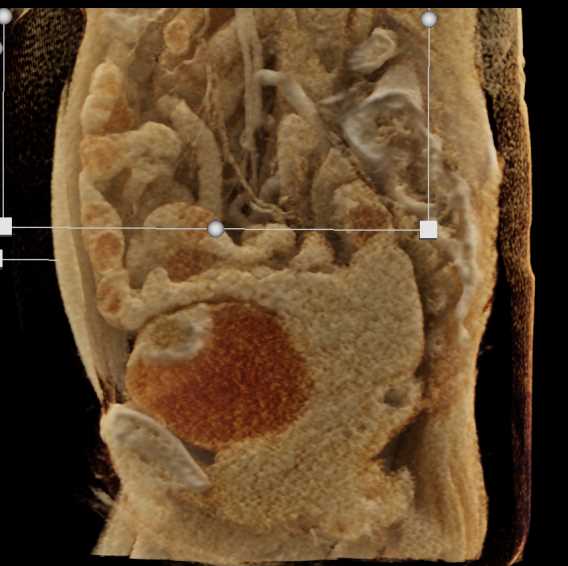

Urachal Carcinoma of the Bladder